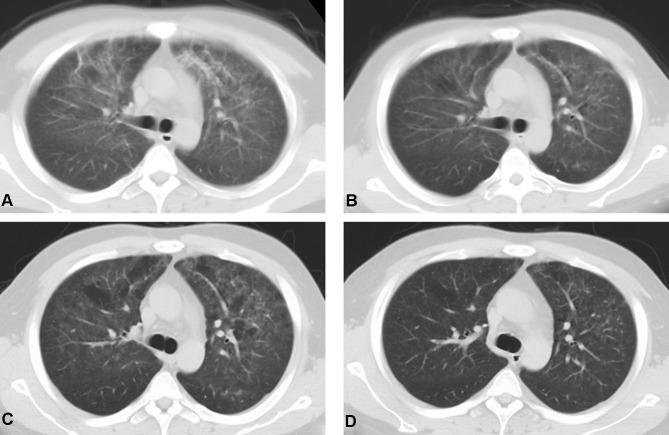

https://cdn.ncbi.nlm.nih.gov/pmc/blobs/2e28/8628180/3395c082fc70/IDR-14-4913-g0001.jpg